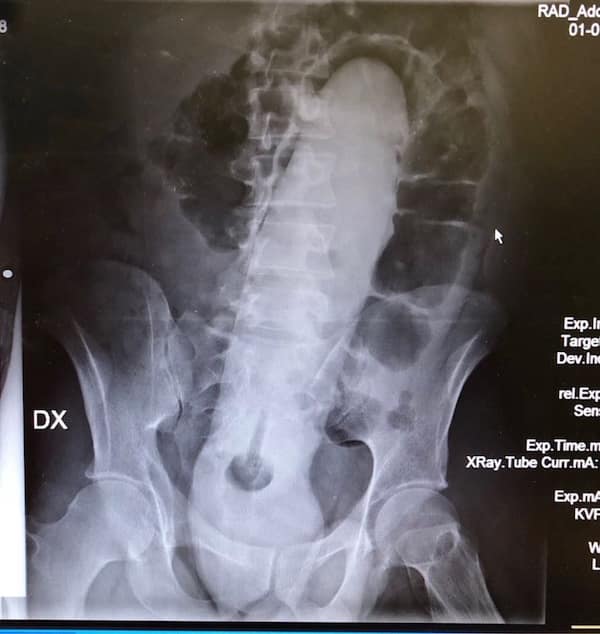

I used to think that nothing could surprise me anymore—until I stumbled upon some weird x-ray photos that made me reconsider my stance on human ingenuity (or lack thereof). Apparently, some people have a knack for getting objects lodged where they absolutely shouldn’t be. If you’ve ever wondered how not to use everyday items, these images might provide some unintended guidance.

This collection showcases 31 bizarre x-ray images that defy logic and anatomy textbooks alike. Each photo reveals unexpected objects making cameo appearances inside the human body, turning medical imaging into a gallery of the absurd. From common household items inexplicably found in unusual places to anomalies that would leave even seasoned doctors scratching their heads, these images offer a perplexing glimpse into the more “creative” side of medical emergencies. They highlight the intersection of curiosity, misadventure, and perhaps a dash of poor decision-making, all captured through the lens of radiology.